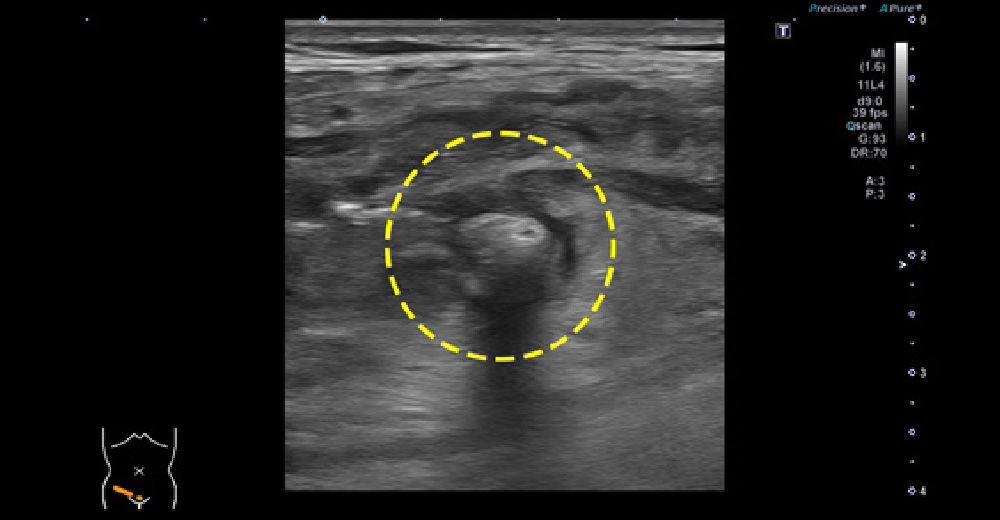

憩室症と憩室炎

憩室炎

上行結腸から背側へ突出した憩室と憩室内結石~腹部エコー